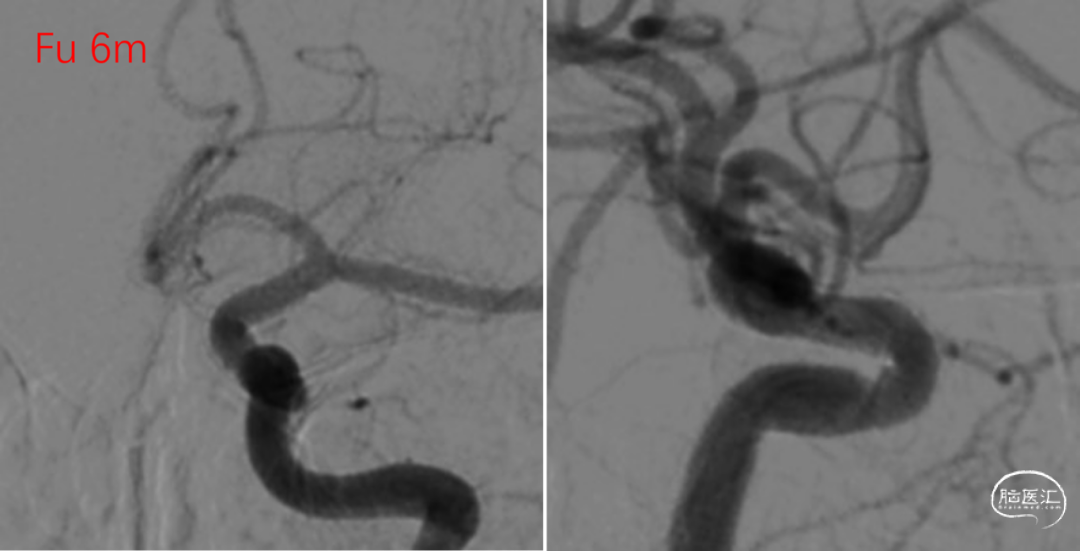

操作过程

常规通路,经Marksman微导管释放,FD推送顺畅,展开良好(图2)。术后Vaso CT显示各部位贴壁良好(图3)。

图.2